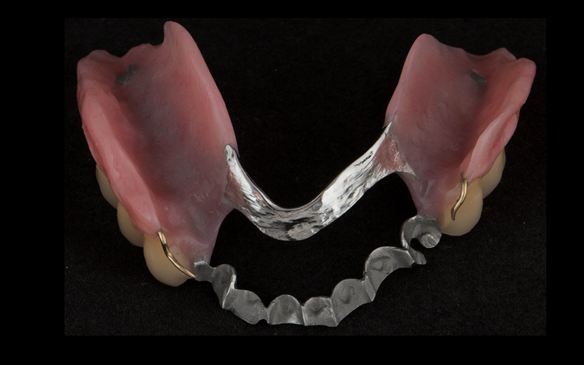

- Definitive dentures (Mk 2) – complete upper metal reinforced and lower cobalt chromium based partial of hygienic Scandinavian design to be made 9 - 12 months after extractions of all upper teeth and LR5 and LL4

The clinical situation and treatment process is shown in detail below with photographs.

The patient has been successfully rehabilitated and is now having periodontal maintenance from Syed Abad, Specialist in Periodontics at the practice. His quality of life has improved considerably. The clinical prosthodontics was provided by me and the technical work by Rowan.